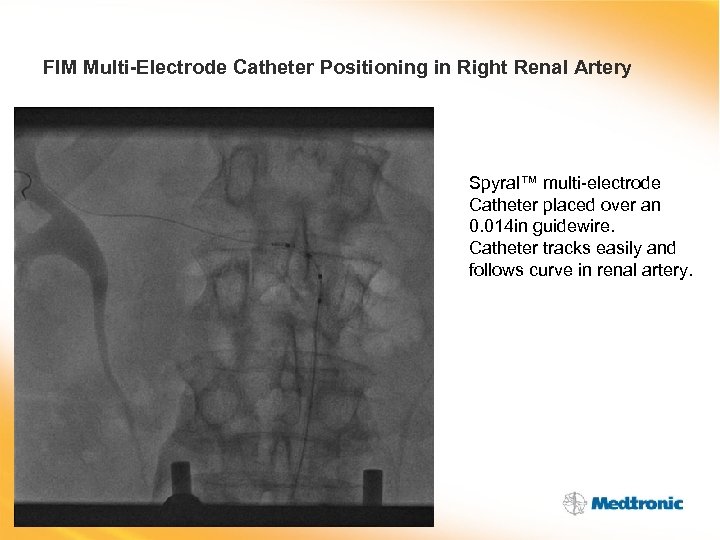

FIM Multi-Electrode Catheter Positioning in Right Renal Artery Spyral™ multi-electrode Catheter placed over an 0. 014 in guidewire. Catheter tracks easily and follows curve in renal artery.

FIM Multi-Electrode Catheter Positioning in Right Renal Artery Spyral™ multi-electrode Catheter placed over an 0. 014 in guidewire. Catheter tracks easily and follows curve in renal artery.

FIM Multi-Electrode Catheter Positioning in Right Renal Artery Spyral™ multi-electrode catheter situated in right renal artery, guide wire keeping catheter ‘straight’.

FIM Multi-Electrode Catheter Positioning in Right Renal Artery Spyral™ multi-electrode catheter situated in right renal artery, guide wire keeping catheter ‘straight’.